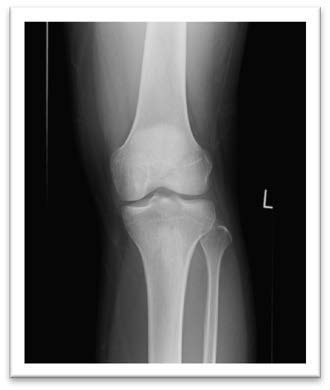

膝正面の写真

膝側面の写真

膝軸位の写真